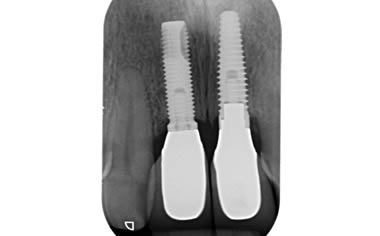

More front teeth replaced by dental implants

Case Three (4 images)